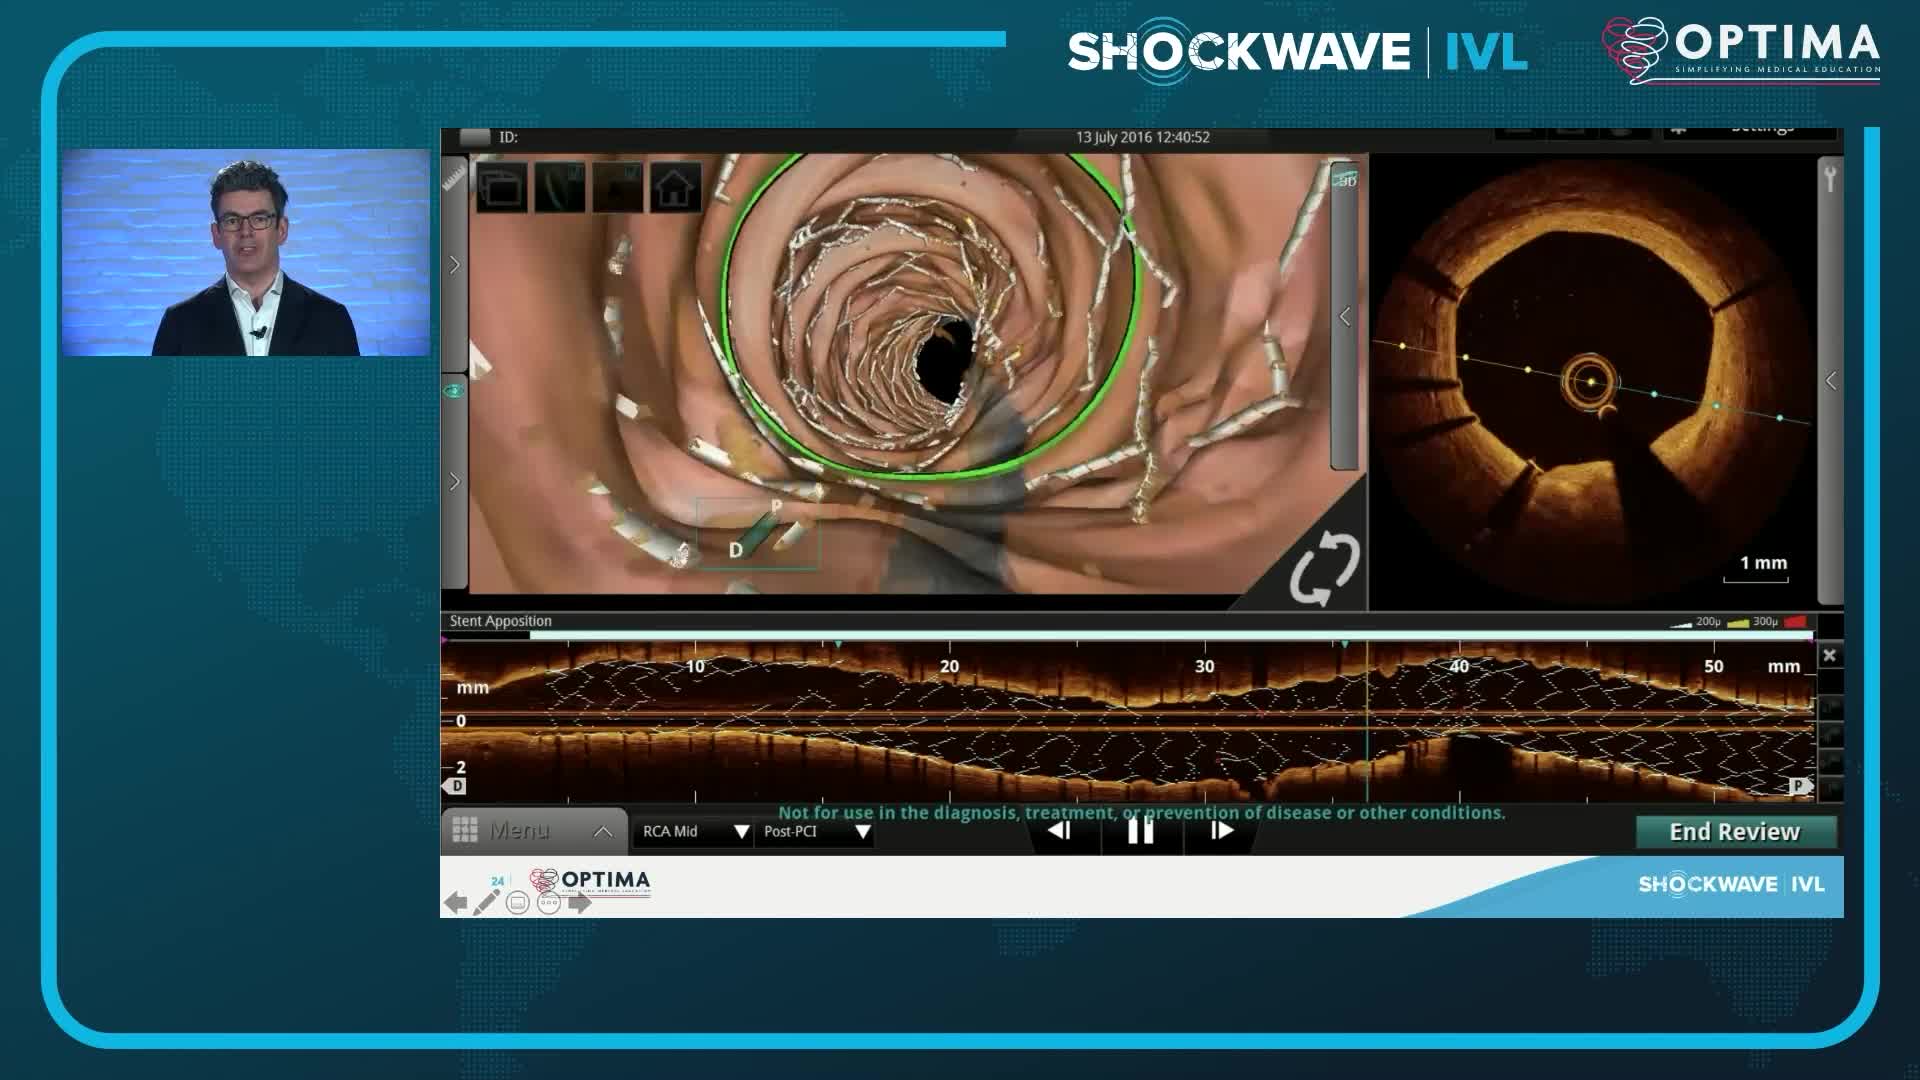

Coronary IVL Greatest Hits

Real-World EU Experience: Coronary IVL Across Different Calcium Morphologies from TCT 2022

Shockwave IVL Coronary Real-World Cases, Outcomes & Algorithms: An InCathLab Webinar